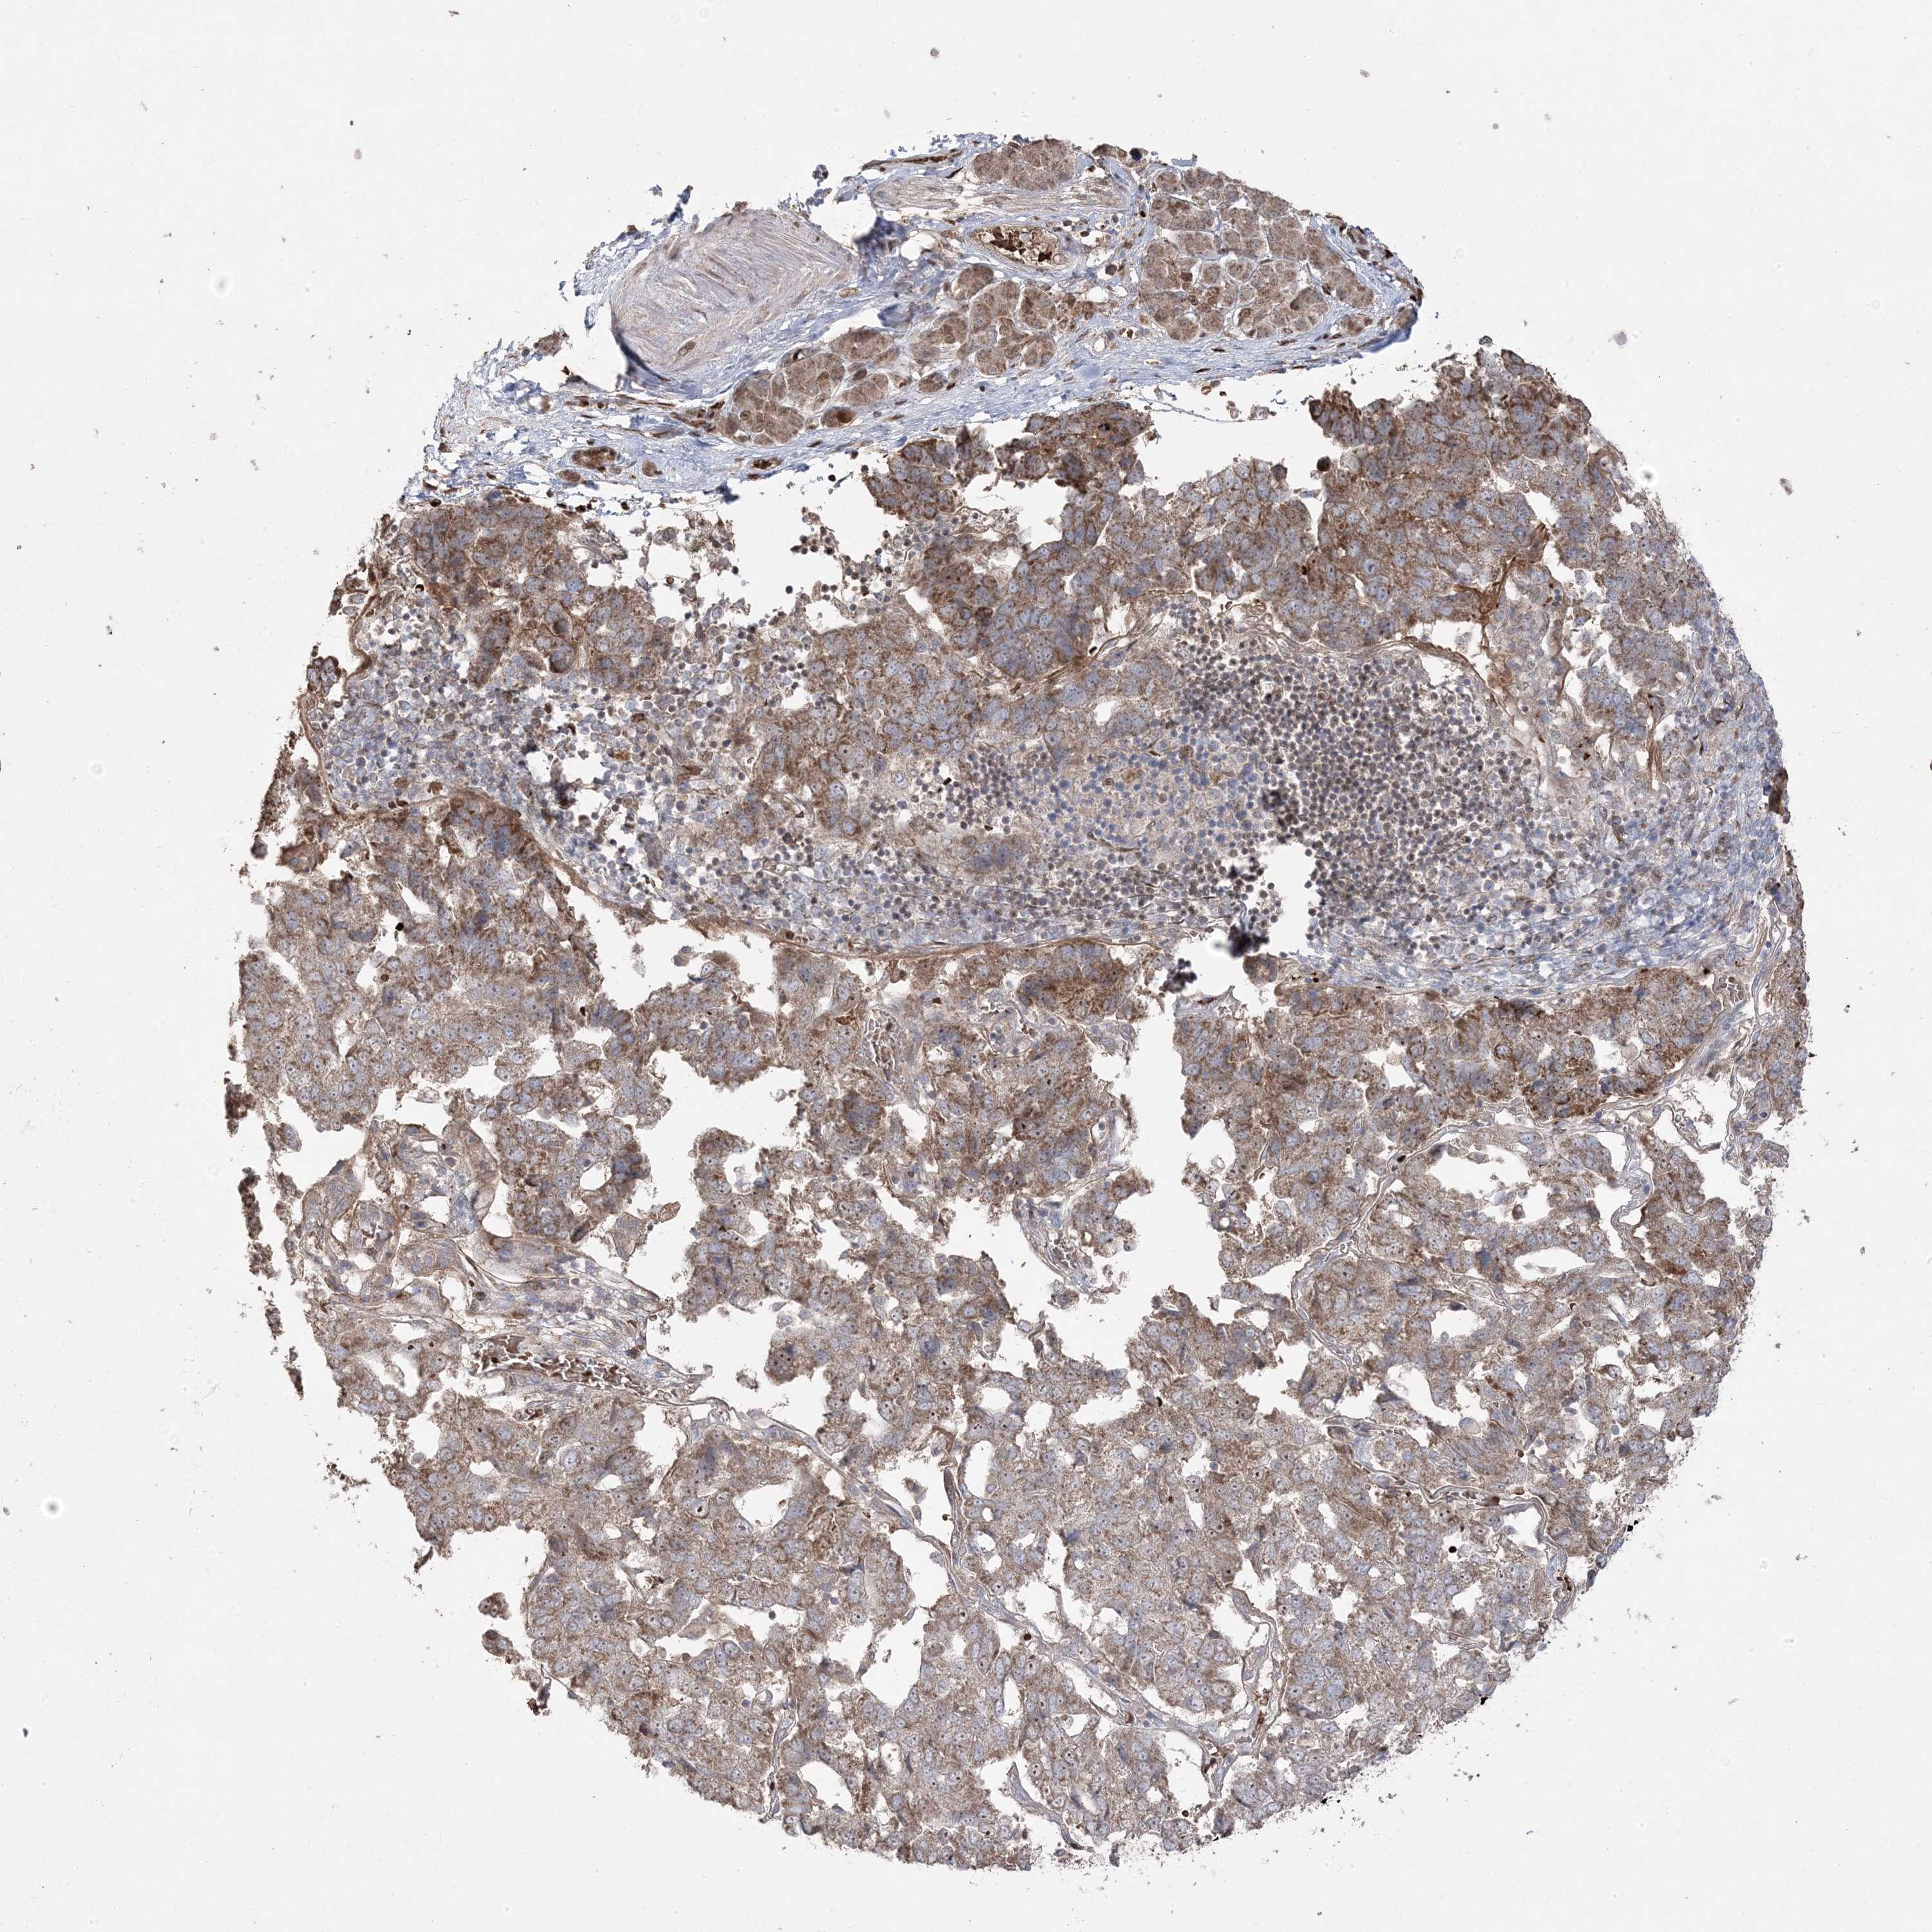

PANCREATIC CANCER - Protein expressioni

A mouse-over function shows sample information and annotation data. Click on an image to view it in a full screen mode. Samples can be filtered based on level of antibody staining by selecting one or several of the following categories: high, medium, low and not detected. The assay and annotation is described here.

Note that samples used for immunohistochemistry by the Human Protein Atlas do not correspond to samples in the TCGA dataset.

Antibody stainingi

Antibody staining in the annotated cell types in the current human tissue is reported as not detected, low, medium, or high, based on conventional immunohistochemistry profiling in selected tissues. This score is based on the combination of the staining intensity and fraction of stained cells.

Each image is clickable and will lead to virtual microscopy that enables deeper exploration of all samples and also displays staining intensity scores, fraction scores and subcellular localization as well as patient and tissue information for each sample.

Antibody HPA030123

Staining

High

Medium

Low

Not detected

Intensity

Strong

Moderate

Weak

Negative

Quantity

>75%

75%-25%

<25%

None

Location

Nuclear

Cytoplasmic/membranous

Cytoplasmic/membranous,nuclear

Adenocarcinoma, NOS